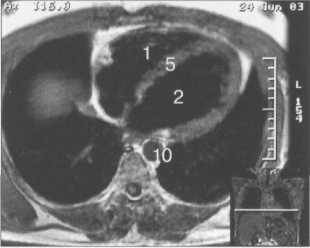

МРТ АНАТОМИЯ СЕРДЦА

МРТ позволяет получать изображения сердца в поперечной (аксиальной), фронтальной (корональной) и сагиттальной плоскостях (ортогональные сечения). Поскольку анатомические оси сердца и магистральных сосудов (за исключением аорты в нисходящем отделе и полых вен) не совпадают со стандартными ортогональными плоскостями исследования, общепринятыми при исследованиях других органов и систем организма, для МРТ-исследования сердечно-сосудистой системы разработаны дополнительные наклонные срезы (двухкамерное сечение, четырехкамерное сечение, сечение по короткой оси левого желудочка).

Рис. 9.47. МРТ сердца. Аксиальная плоскость.

Здесь и на рис. 9.48—9.52:

I — правый желудочек, 2 — левый желудочек, 3 — правое предсердие, 4 — левое предсердие, 5 — межжелудочковая перегородка, 6 — межпредсердная перегородка, 7 — задняя стенка левого желудочка, 8 — восходящая часть аорты, 9 — дуга аорты, 10 — нисходящая часть аорты, 11 — легочный ствол, 12 — правая легочная артерия. 13 — левая легочная артерия, 14 — верхняя полая вена, 15 — нижняя полая вена, 16 — трахея.

Рис. 9.51. МРТ сердца. Сечения по короткой оси левого желудочка.

На рис. 9.47—9.52 представлены Т1-ВИ наиболее часто используемых МР-сечений сердца.